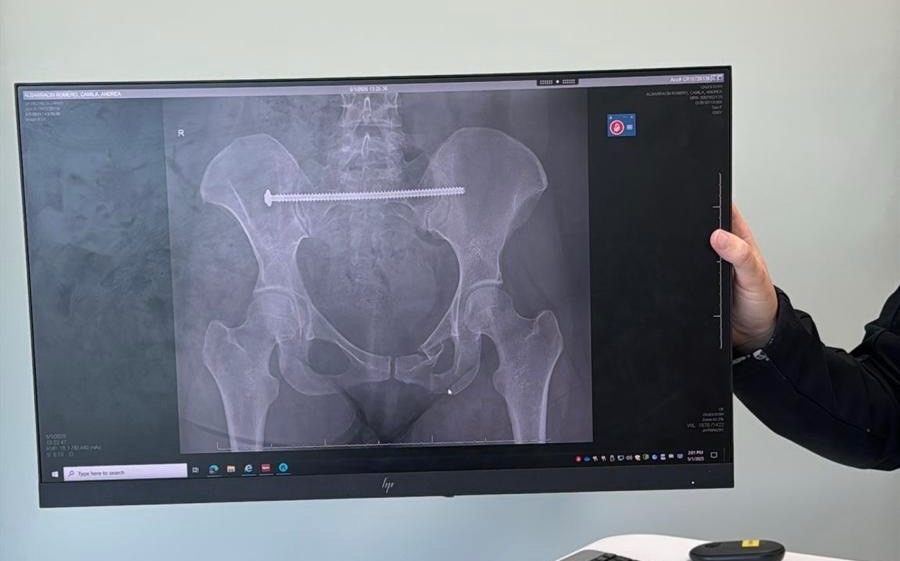

She was dragged under the vehicle, then crushed by the rear tire. The impact shattered her pelvis in three places and broke her left ankle in two. Camila spent 9 days in the hospital and underwent two major surgeries to begin repairing the damage.

Camila fue arrastrada por debajo del auto y luego aplastada por la llanta trasera. El impacto le destrozó la pelvis en tres partes y le rompió el tobillo izquierdo en dos. Pasó 9 días en el hospital y se sometió a dos cirugías mayores para comenzar a reparar el daño.